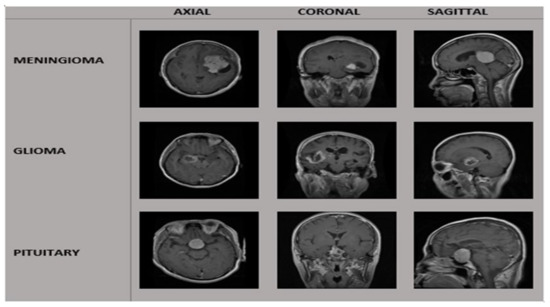

3.1. Dataset and Preprocessing

| Tumor Class | Patients | Images | View of MRI. | No. of MRI. Images |

|---|---|---|---|---|

| Meningioma | 82 | 708 | A * | 209 |

| C * | 268 | |||

| S * | 231 | |||

| Pituitary | 62 | 930 | A * | 291 |

| C * | 319 | |||

| S * | 320 | |||

| Glioma | 89 | 1426 | A * | 494 |

| C * | 437 | |||

| S * | 495 | |||

| Total | 233 | 3064 | 3064 |